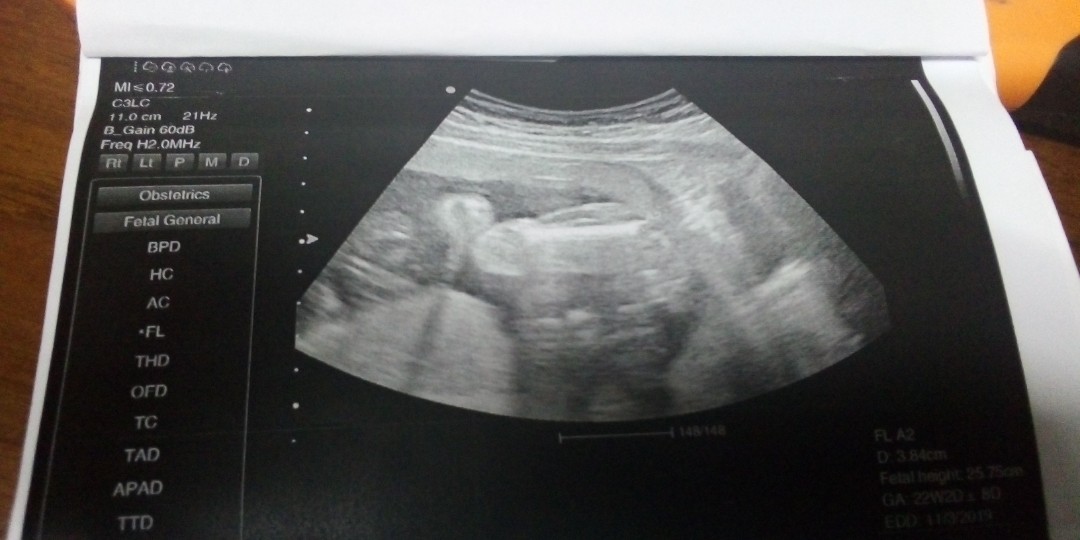

ซาวด์ตอน5เดือนคะ

ตามด้วยคนเลยค่ะ

ซาวน์ตอน21+3วีค